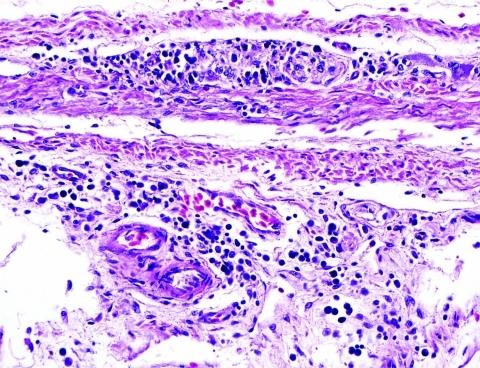

Avian bornavirus (ABV) is a newly discovered member of the family Bornaviridae that has been associated with the development of a lethal neurologic syndrome in birds, termed proventricular dilatation disease (PDD). We successfully isolated and characterized ABV from the brains of 8 birds with confirmed PDD. One isolate was passed 6 times in duck embryo fibroblasts, and the infected cells were then injected intramuscularly into 2 healthy Patagonian conures (Cyanoliseus patagonis). Clinical PDD developed in both birds by 66 days postinfection. PDD was confirmed by necropsy and histopathologic examination. Reverse transcription-PCR showed that the inoculated ABV was in the brains of the 2 infected birds. A control bird that received uninfected tissue culture cells remained healthy until it was euthanized at 77 days. Necropsy and histopathologic examinations showed no abnormalities; PCR did not indicate ABV in its brain tissues.

禽源博尔纳病毒(ABV)是刚发现的博尔纳病毒科的一个新成员,与鸟类致命性神经系统疾病——又称前胃扩张病(PDD)的发生有关。我们从 8 只确诊患有 PDD 的病鸟脑中成功分离并鉴定出 ABV。其中一个分离株在鸭胚成纤维细胞中传代 6 次,然后将感染的细胞肌肉内注射到 2 只健康的巴塔戈尼亚鹦鹉(Cyanoliseus patagonis)中。感染后第 66 天,2 只鸟均出现临床 PDD。剖检和组织病理学检查证实了 PDD。反转录-PCR 显示接种的 ABV 存在于 2 只感染鸟的大脑中。接种未感染的组织培养细胞的对照鸟直到 77 天被安乐死时仍保持健康。剖检和组织病理学检查未显示任何异常;PCR 也未在其脑组织中检测到 ABV。